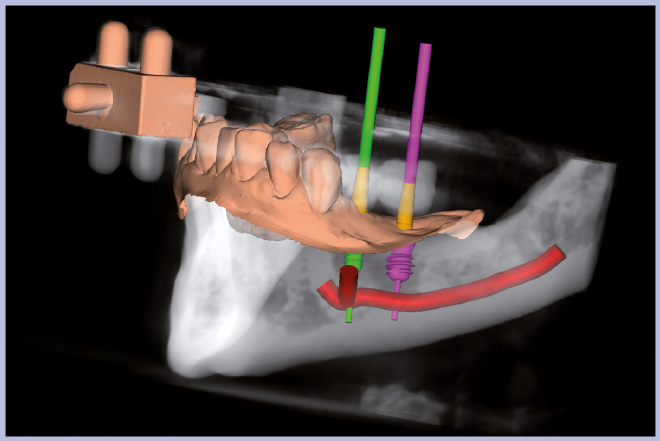

Per riabilitare la masticazione del terzo quadrante, con osso gravemente atrofico, si procede allo studio del caso con esame radiologico 3D e posizionamento virtuale di impianti Exacone® Leone. La prima valutazione è stata eseguita con il software dell’apparecchio radiografico Cone Beam presente in studio. Dopo aver verificato che la quantità di osso residuo fosse sufficiente all’inserimento di due impianti, seppur di dimensioni ridotte, in sede 3.5 e 3.6 senza l’ausilio di tecniche di rigenerazione ossea (Figg. 1-3), si richiede al laboratorio di confezionare una mascherina radiologica con ceratura diagnostica radiopaca e repere standardizzato a livello incisale come da protocollo Leone (Figg. 4, 5). Si verifica quindi clinicamente l’assenza di mobilità della mascherina dopo il posizionamento nel cavo orale del paziente (Figg. 6, 7). Si effettua una CBCT con la mascherina in posizione e l’esame viene inviato in formato DICOM all’azienda Leone assieme al modello master della paziente. L’azienda provvede quindi ad inviare agli Autori il software 3Diagnosys (software di progettazione) in licenza monopaziente con caricati i file DICOM ricevuti; il software viene quindi utilizzato per la progettazione definitiva del caso (Figg. 8-12).

- Figg. 8-12 – Pianificazione implantare con software 3Diagnosys Leone

- Fig. 9

- Fig. 10

- Fig. 11

- Fig. 12